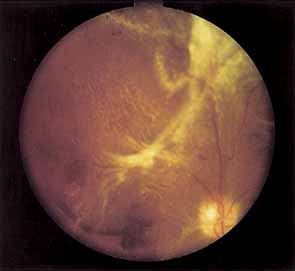

As demonstrated by increased latency and decreased amplitude of the visual evoked potential, many patients with diabetes without retinopathy have subclinical optic neuropathy.269,270 In addition, patients with diabetes can develop two types of acute optic neuropathy. The first, anterior ischemic optic neuropathy (AION) is identical to that seen in patients without diabetes. The patients report a sudden decrease in visual acuity or a sudden visual field loss.271–273 The main ocular finding is a “pale swelling” of the optic nerve head with, considering the degree of disc edema, very few hemorrhages (Fig. 27). On fluorescein angiography segmental nonfilling or slow filling is seen (Fig. 27). An afferent pupillary defect (Marcus Gunn) is nearly always present. Visual fields commonly show altitudinal or nerve fiber bundle defects. The disc progresses to optic atrophy (Fig. 27), and improvement in visual function is rare.

Fig. 27 A. Right eye: ischemic optic neuritis. Note pale swelling of optic disc and blurring of disc margins. Left eye: normal disc. B. Fluorescein angiogram. Note poor filling on disc inferotemporally as compared with the rest of the disc. C. Right eye 6 months after optic neuritis. Note slight pallor.